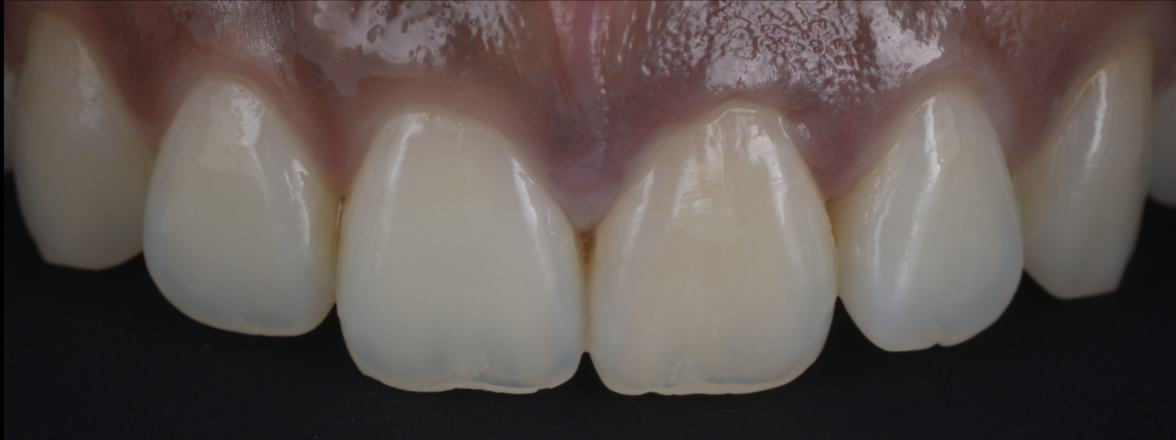

治療後

歯の保存、嚢胞の摘出、審美的改善